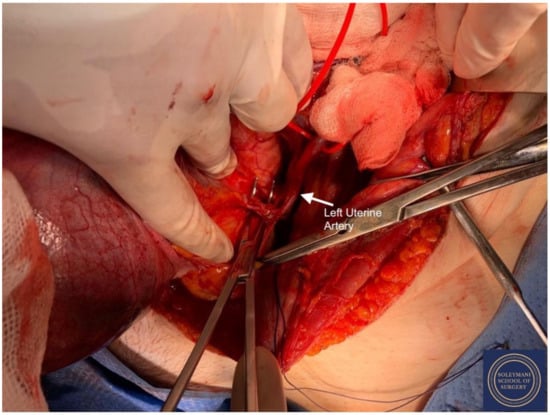

- The uterine arteries were identified at origin and secured (Figure 10). The peritoneum of the pouch of Douglas was incised and the anterior mesorectum was separated from the posterior vaginal wall with division of Dennonveiliers fascia down to the mid-vagina. Laterally, the mesorectum was separated from the uterosacral ligaments to the level of the inferior hypogastric plexus, which was subsequently mobilized from these ligaments from both proximal and lateral aspects (Figure 11). Immediately above the superior margin of the inferior hypogastric plexus, the rectouterine ligaments and uterosacral ligaments were subsequently transected in a stepwise fashion.

- -